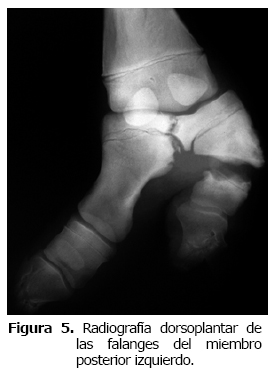

También, se observó una desviación del eje del dígito III hacia medial en la articulación metacarpofalángica, con desprendimiento lateral a nivel de la fisis del cartílago de crecimiento proximal de la P2 y una fractura de tipo Salter Harris 2, con signos de reparación, además, había signos de osteolisis en la P3 del dígito III. En ambos miembros posteriores, se observaba un dígito supernumerario, el cual se originaba a nivel de la articulación metatarsofalángica, ambos dígitos estaban formados por tres falanges y se articulaban con el hueso metatarsiano III (Mt3), uno en la carilla articular lateral y el otro en la medial, la P1 de ambos dígitos en los dos miembros se encontraban parcialmente fusionados en proximal. También se observaba que el crecimiento de ambos dígitos era del mismo tamaño hasta distal y que presentaban el hueso sesamoideo distal. No se pudo determinar cual era el dedo principal. En el miembro posterior derecho (Figura 4) la vista lateromedial permitió observar una deformación flexural marcada hacia plantar a nivel de articulación interfalángica proximal, por luxación completa de esta articulación en ambos dedos (hiperextensión). En el miembro posterior izquierdo (Figura 5) en la vista dorso plantar se observó pérdida del eje podofalángico normal visto de frente, con un quiebre hacia lateral (varus) en ambos dígitos y pérdida de arquitectura en ambas P3, especialmente en la zona del dedo. Además, se observó signos de osteolisis en la zona de fusión parcial de ambas P1. En el dígito lateral se observó una fractura de la primera falange, con signos de osteolisis severa. En la vista latero medial se observó una fractura de P1 en el dígito lateral, con signos de lisis ósea y presencia de aire o gas, concordante con osteomielitis.